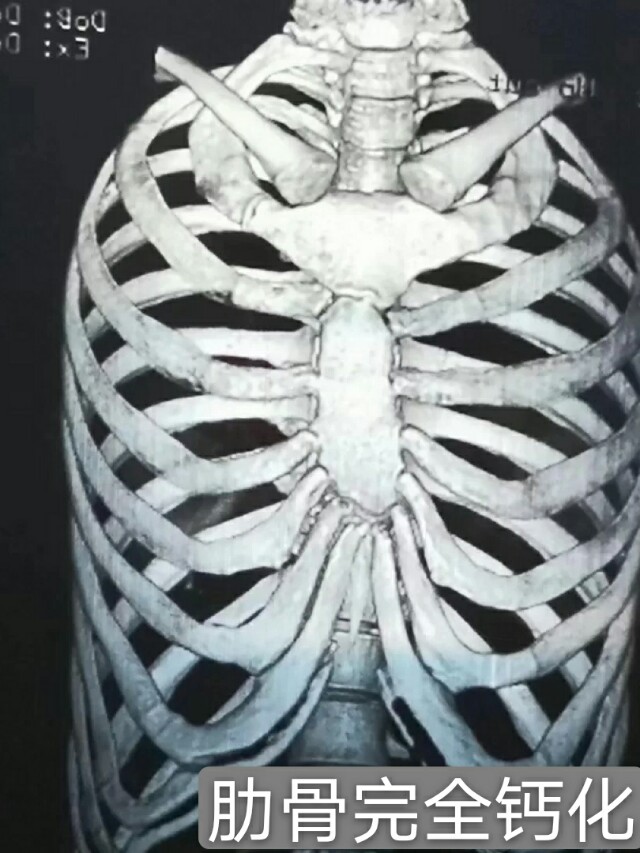

【肋软骨钙化还可以用来隆鼻吗⁉️】

不知道有没有集美遇到这种情况,去医院准备好一切了,检查肋骨的时候。被告知肋骨钙化了,不能用。

是因为钙化后的软骨,不具备肋软骨的特性了。变得比之前更坚硬,而且抗感染性会变得很差,同时细节的雕刻,和术后的缝合很困难,会严重影响术后的效果。

✔️:轻微的钙化,一样可以用来做鼻综合的支架,一般胸片图的肋软骨位置,显示的是点状白色,那移植的软骨基本不会再钙化。

✔️:如果钙化严重,那只能放弃了。建议考虑鼻中隔软骨搭配耳软骨,这也是可以的。如果实在不行,是可以考虑异体骨的。